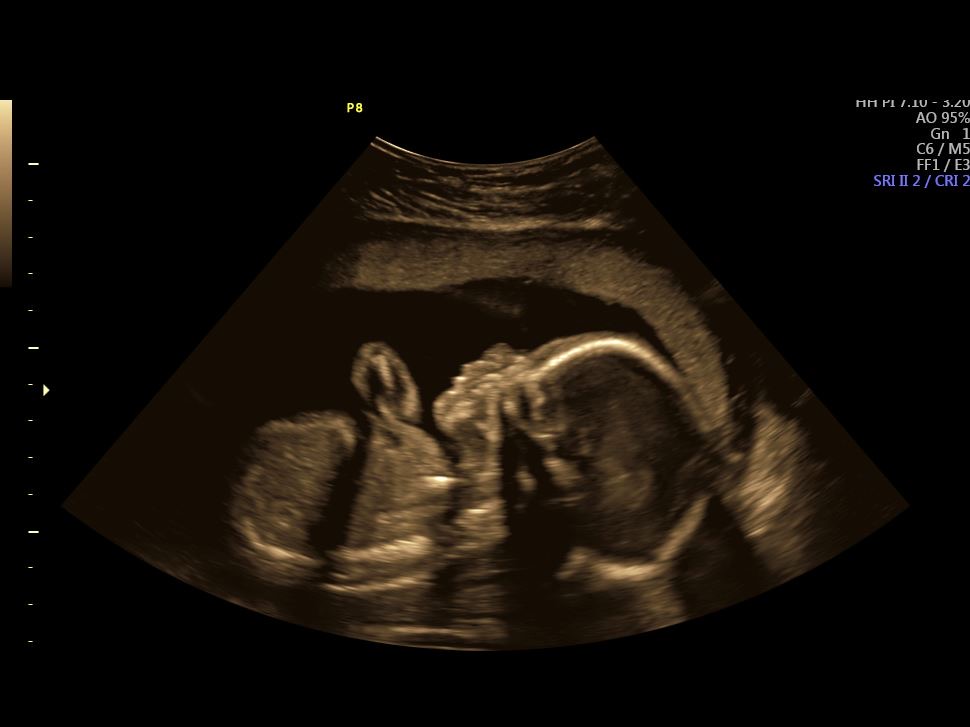

Anatomy Ultrasound: July 28th, 2022

I had started to feel baby movement the week prior to the ultrasound which was really exciting. However, they were still too subtle for Hoch to feel.

So we were both looking forward to checking in and seeing how the baby was doing.

Once it started, Hoch just sat quietly the entire time, mouth gaping under his face mask, while the technician took baby measurements.

At the end, he was like, “we need one of these machines at home!”

The doctor said everything looked PERFECT! Baby Shin weighed in around 1 lb 2 oz (in the 90th percentile) and her heart rate was 143 bpms.

I was 21 weeks during this Ultrasound.